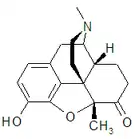

Morphinones and morphols

Structures

| Morphinones and morphols | ||||

|---|---|---|---|---|

Codeinone Codeinone |

Hydrocodone Hydrocodone |

Hydromorphone Hydromorphone |

Oxycodone Oxycodone |

Oxymorphone Oxymorphone |